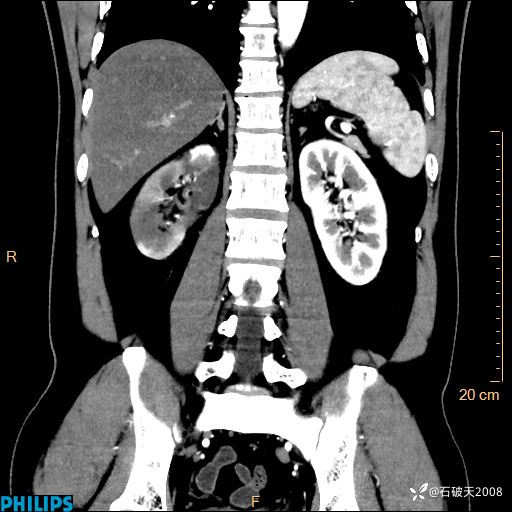

这个病例诠释了“腹部不增强,等于耍流氓”

增强轴位